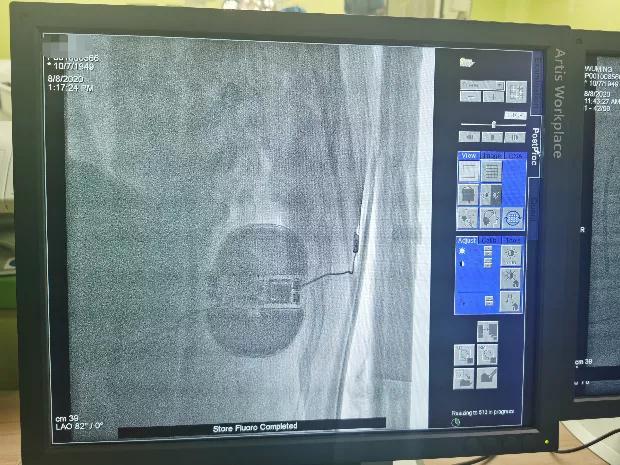

手术在全麻醉下进行,于左侧第5肋间沿腋中线走形切开皮肤6厘米,逐层分离皮下组织至肌层,寻找到背阔肌与前锯肌之间的深筋膜层,钝性分离,做好囊袋确保足够深度来容纳装置。

于剑突下切开皮肤2cm,逐层分离皮下组织至筋膜层,通过隧道穿引针连接囊袋,再沿胸骨向上约14cm处切开皮肤1cm,逐层分离皮下组织至筋膜层,通过隧道穿引针连接剑突下切口,使用隧道穿引针将45cm长的3501除颤电极从囊袋经隧道送至剑突下切口,固定电极中段,再使用隧道穿引针将电极经隧道送至胸骨上方切口,固定头端。连接脉冲发生器A209,置入囊袋内,逐层缝合筋膜层及皮下组织,进行DFT测试,采用50HZ,200MA交流电方式进行诱颤,SICD正确识别,经首次65J除颤成功,除颤阻抗58欧姆。缝合皮肤 ,术区纱布覆盖,包扎,弹力绷带加压包扎止血。手术圆满成功,耗时约1小时。